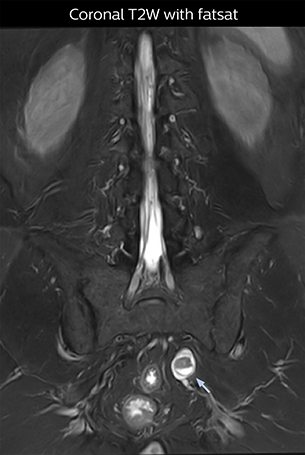

“NerveVIEW is really useful for those cases where a nerve disorder is strongly suspected based on the clinical examination but our regular MRI images do not show any findings. These atypical herniations and spinal canal stenosis, occurring in 5% to 15% of the total lumbar herniation/stenosis cases are our main target when using NerveVIEW,” says Dr. Yabuki.

“The intra-luminal signal of veins, especially around the intervertebral space, can be suppressed well with NerveVIEW. As a result, we can easily observe the detailed nerve structure around the posterior ganglion,” he says. “This is why we use 3D NerveVIEW for intraforaminal stenosis and extraforaminal stenosis/herniation (lateral disc herniation). On the other hand, if herniation is suspected to exist inside the dorsal root ganglion (DRG), balanced TFE or ProSet-FFE is applied. NerveVIEW is not suitable for evaluating the median type of herniation.” The SE-EPI DWI-based method for MR neurography works well for large FOV exams like whole-body MRI, but focal examination of nerves is often limited by the attainable spatial resolution (both inplane and slice direction) and geometric distortion. “3D NerveVIEW achieves higher in-plane resolution – close to our other routine spine sequences – and the source images can be used instead of adding a fat-suppressed T2-weighted sequence,” Tanji says.

“Recently, the two surgical methods extreme and oblique lateral interbody fusion (XLIF and OLIF) have become mainstream for minimally invasive treatment of lumbar spinal canal stenosis and intervertebral foramen stenosis. With these surgical techniques, the spine is approached from the flank, and prior knowledge of the exact anatomy of the lumbosacral plexus would be extremely helpful. To that end, high slice resolution (less than 1 mm acquisition) that enables sharper sagittal MPR images will be needed.”